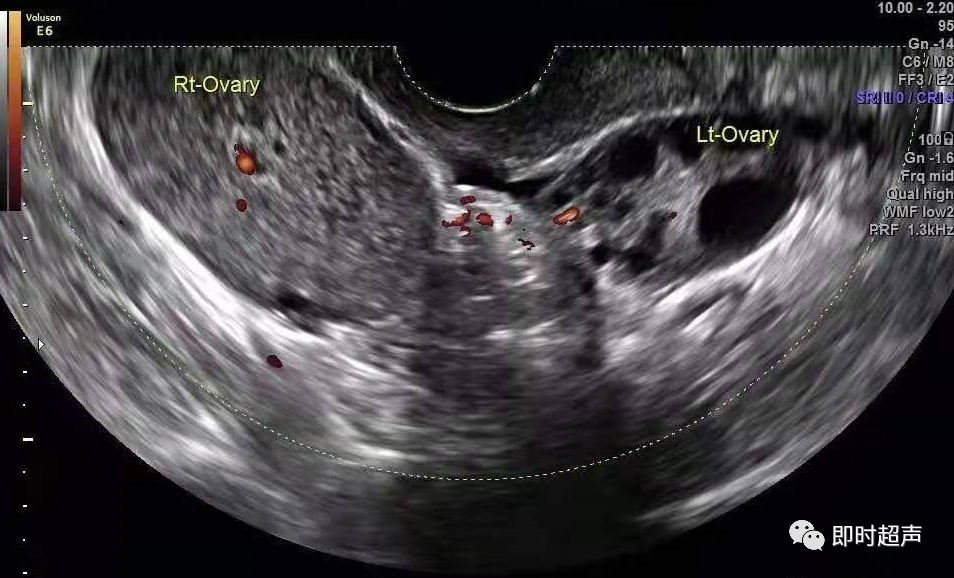

(5)卵巢囊肿>5 cm(25 分)图 3 卵巢纤维卵泡膜细胞瘤扭转:患者 55 岁